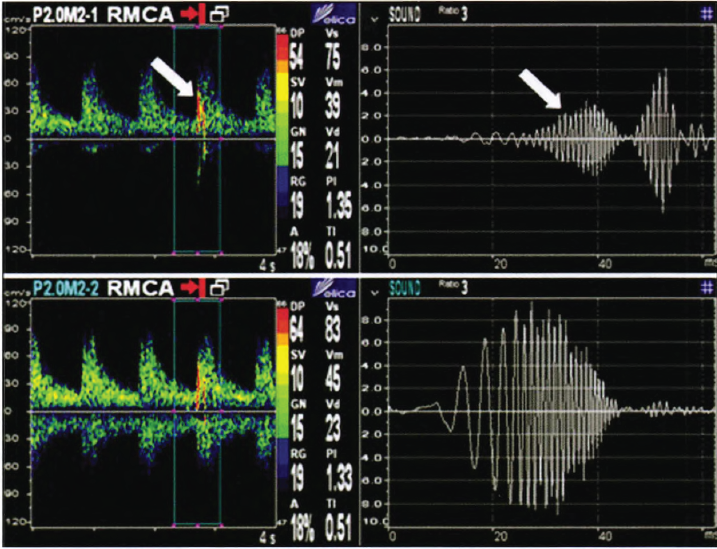

经颅多普勒监测MES声谱图